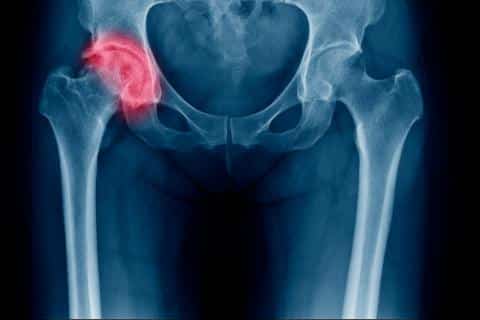

Una caída que derive en rotura de fémur o cadera a partir de los 65 años aumenta el riesgo de morir en un año.

Especialistas dieron a conocer que caer en esta condición es más grave de lo que se piensa, ya que la probabilidad de fallecer en un año aumenta entre un 15 y un 30 por ciento.

En realidad, la persona que sufre dicha lesión no solo se ve afectada por la fractura, sino también por todas las complicaciones que pueden derivarse.